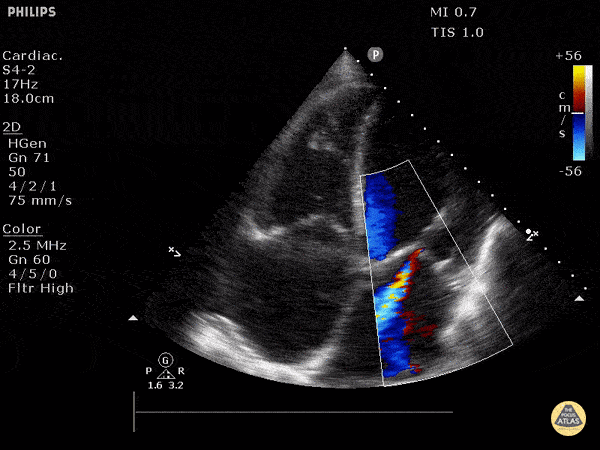

Valve Regurgitation